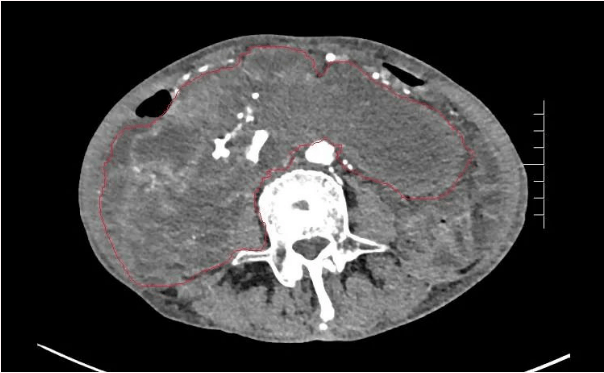

患者王大爺,男,72歲,發(fā)現(xiàn)腹腔腫物10余年,近兩年來患者雙下肢乏力、貧血,依靠間斷輸血維持著正常生活,出現(xiàn)頭昏,行動(dòng)困難,腹部疼痛及便血慕名來我院就診。入院后查體評(píng)估患者年齡大,體質(zhì)差,嚴(yán)重貧血,肺部感染及腸梗阻征象,腹部增強(qiáng)CT檢查提示腹膜后巨大腫瘤,長徑超過30厘米,占據(jù)大部分腹腔,并可能存在雙原發(fā)腫瘤。

苗滿園腫瘤外科團(tuán)隊(duì)在麻醉科/手術(shù)室的緊密配合下為該患者進(jìn)行手術(shù),術(shù)中發(fā)現(xiàn)腫瘤巨大,幾乎占據(jù)了整個(gè)腹腔,從左側(cè)向右腹腔延伸,向上將肝、腎擠向膈下,向左將胃及小腸擠向左上腹,向下深達(dá)盆腔內(nèi),包繞下腔靜脈、腸系膜上動(dòng)脈等大血管及輸尿管,回盲部及回腸也受侵犯。手術(shù)難度巨大,風(fēng)險(xiǎn)極高。團(tuán)隊(duì)?wèi){借著高超的手術(shù)技能和精準(zhǔn)的手術(shù)預(yù)案沉著應(yīng)對(duì),迎難而上,應(yīng)用高頻電刀、超聲刀、切割縫合器等先進(jìn)設(shè)備,耗時(shí)近5小時(shí)為患者切除了巨大腹腔腫瘤,并聯(lián)合右半結(jié)腸切除,術(shù)中出血僅50ml。術(shù)后病理為腹膜后巨大平滑肌瘤+回腸腺癌。